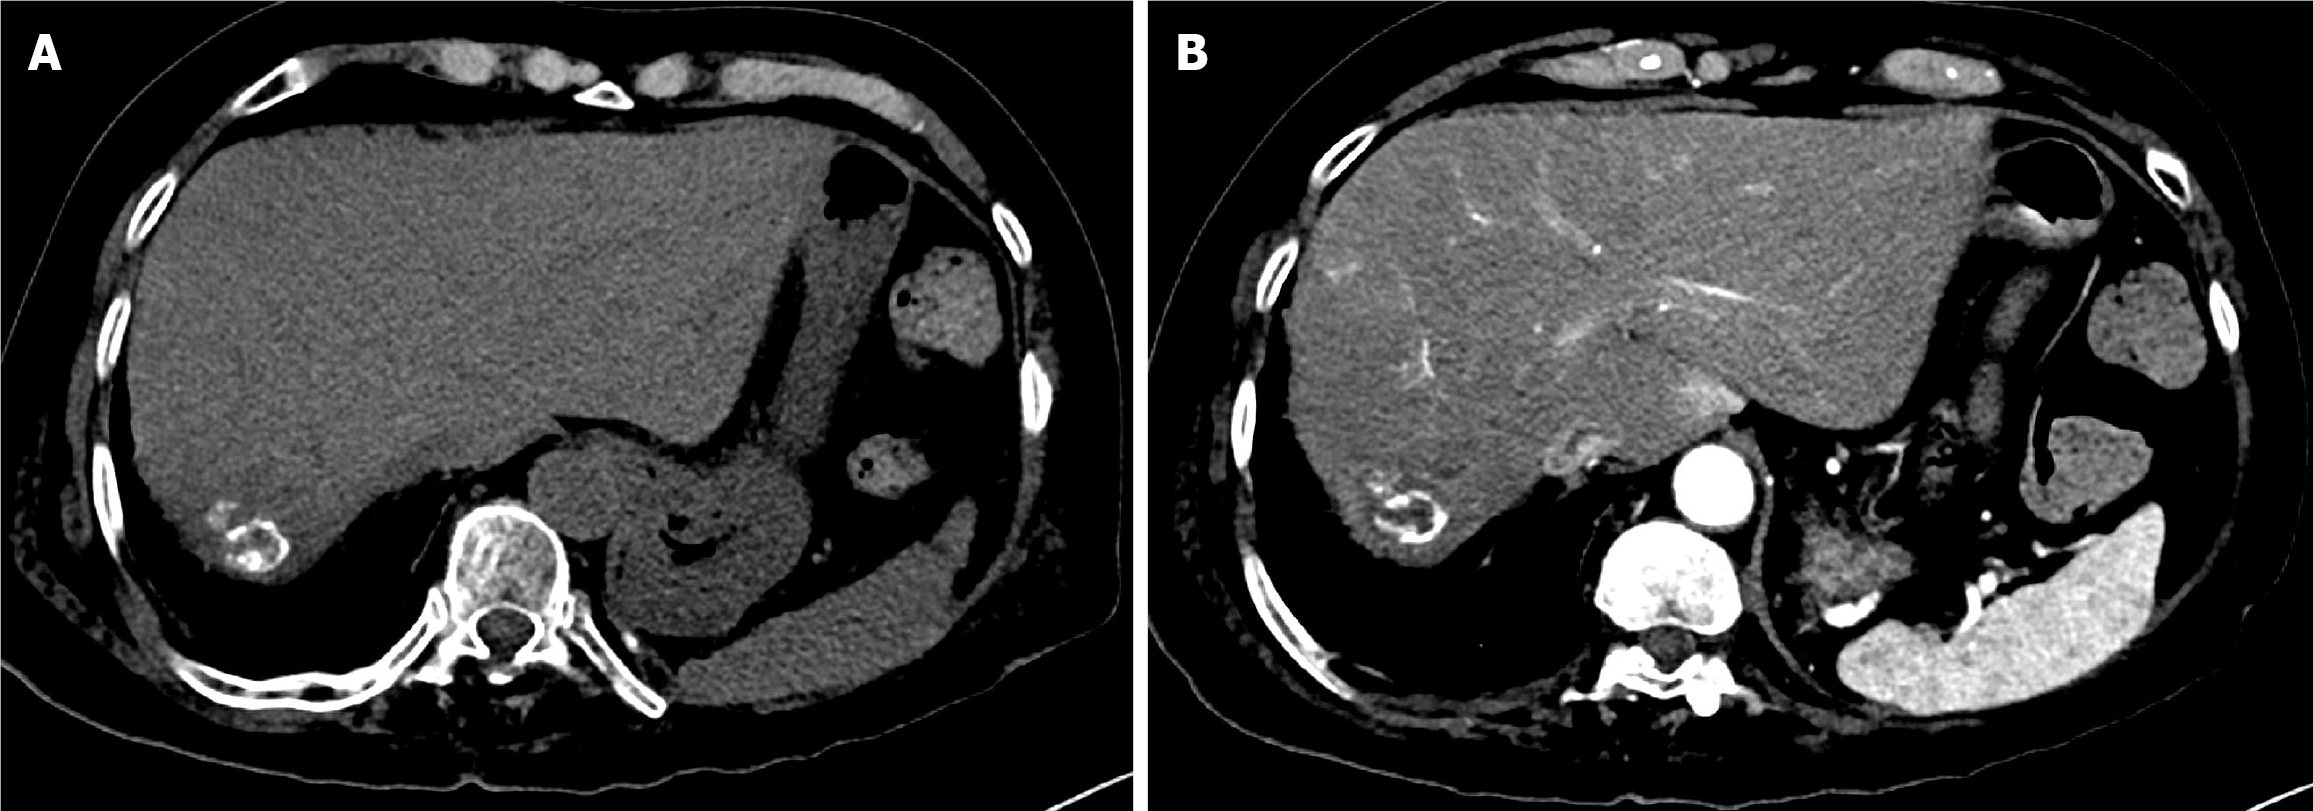

Figure 11 One-year follow-up computed tomography of the abdomen after the second drug-eluting bead transarterial chemoemboli zation in Case 2.

A: Pre-contrast computed tomography (CT) demonstrated faint linear peripheral calcification of the treated hepatic mass; B: Arterial phase CT showed a non-enhancing mass, consistent with complete response.